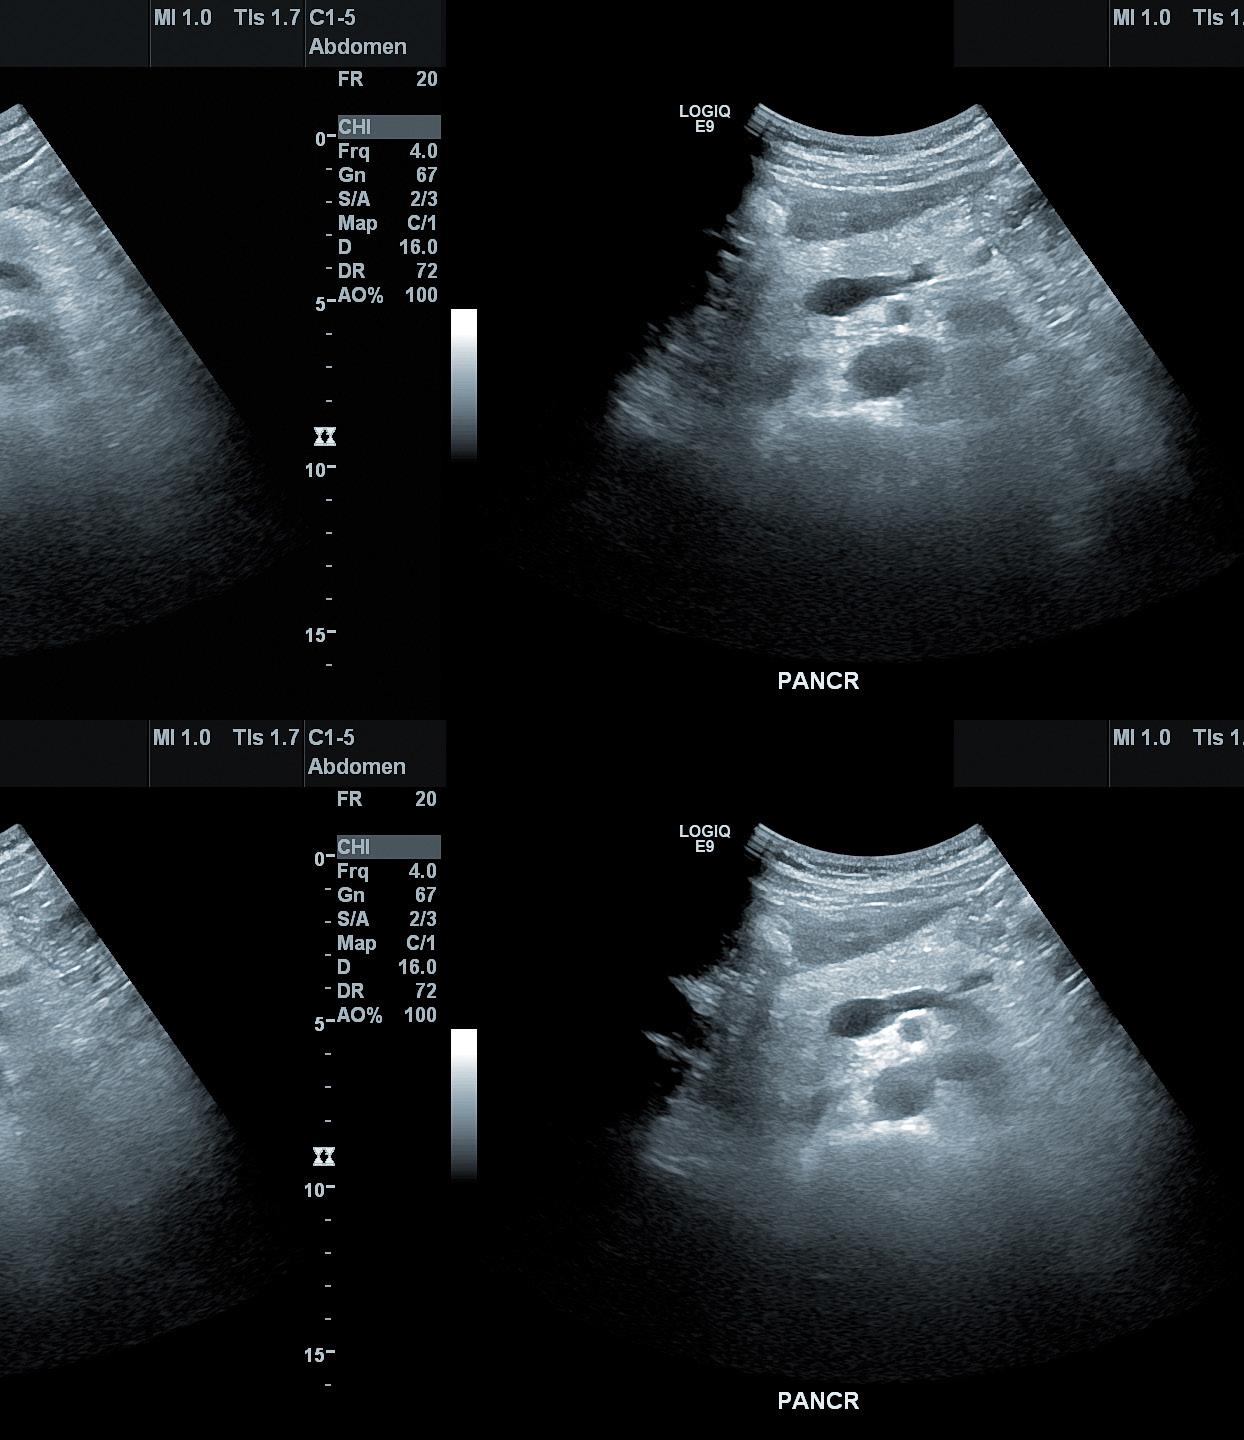

• Interpreted CT, MRI, radiography, and ultrasound images of abdomen and pelvis

• Performed advanced imaging examinations including contrast enhanced ultrasound (CEUS)

• Performed fluoroscopic examinations of gastrointestinal and genitourinary systems, including feeding tube placement

• Streamlined protocoling of contrast-enhanced ultrasonography service with Lumason® with multiple procedures monthly

• In conjunction with UK’s nephrology team, seamlessly transitioned ultrasound-guided biopsies of native and transplant kidneys to interventional nephrology

• In conjunction with UK’s pathology team, incorporated routine collection of Afirma samples for molecular testing for all thyroid biopsies

• UK Good Samaritan Hospital radiology ultrasound granted ACR ultrasound renewal through April 2028 for obstetrical (first trimester only), gynecological, general, and vascular (abdominal and peripheral)